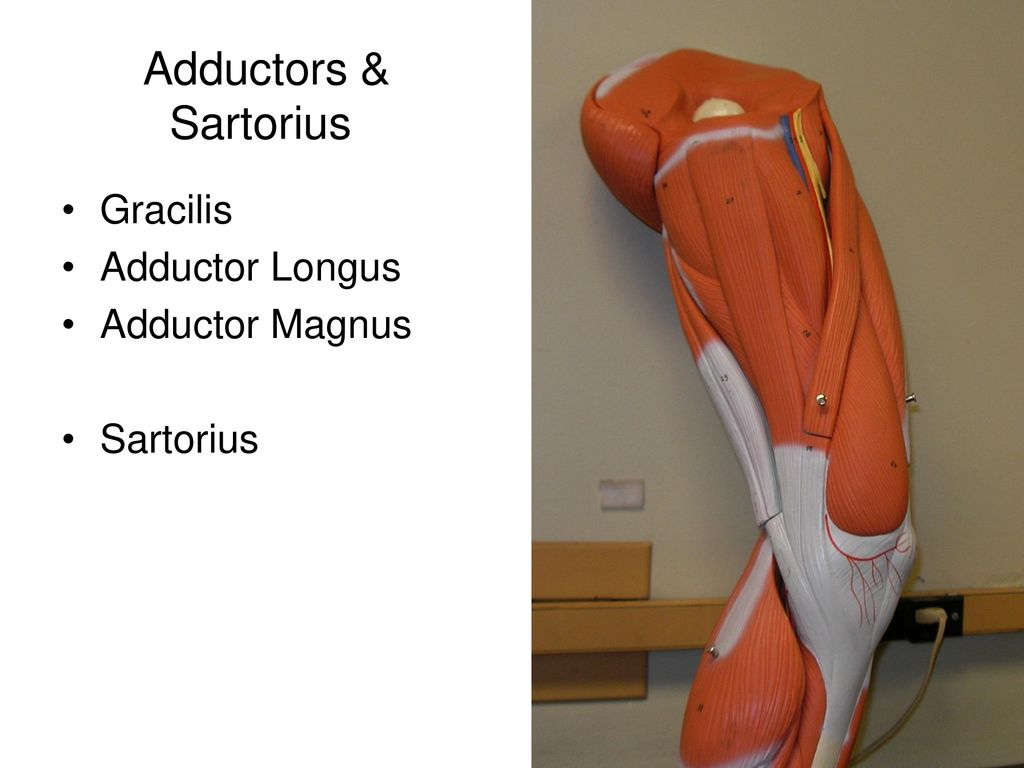

Анатомия и Функции Мышцы Adductor Magnus